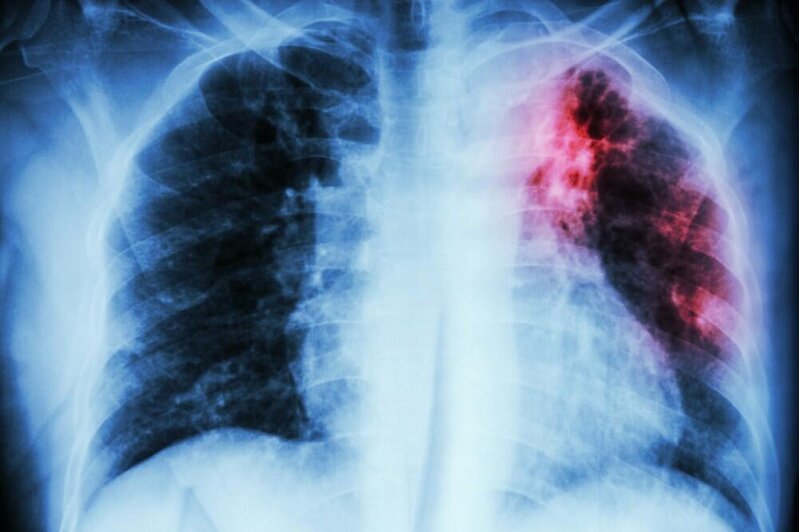

Ölkəmizdə vərəmlə bağlı statistika AÇIQLANDI

Azərbaycanda vərəmlə xəstələnmə dinamikası (100.000 əhaliyə): 2015 ildə bu göstərici 41.1 olan halda, 2025 ildə - 21,5 qeyd olunub.

Azərbaycanda ilkin ağciyər vərəmli xəstələr arasında TDM-nin (Turşuya Davamlı Mikobakteriya - Vərəm Mikobakteriyası) aşkar olunması dinamikası 2015 ildə 53% olduğu halda, 2025 ildə bu göstərici 86% çatıb.

"Həm həssas, həm də Dərmanlara Davamlı Xəstələrin müalicə göstəriciləri daha yüksək olub. Uşaq və yeniyetmələrin vərəmlə xəstələnmə göstəriciləriləri əhəmiyyətli dərəcədə yaxşılaşıb. Əgər 2015 ildə ölkədə 369 uşaq və yeniyetmə vərəm ilə xəstəlinmişdisə, 2025 ildə xəstələnən uşaq və yeniyetmələrin sayı 198 olub. Hətta 2024 il üçün bu göstəriçi 278 idi, bu da əhəmmiyətli dəyişiklik olduğunun sübutudu".